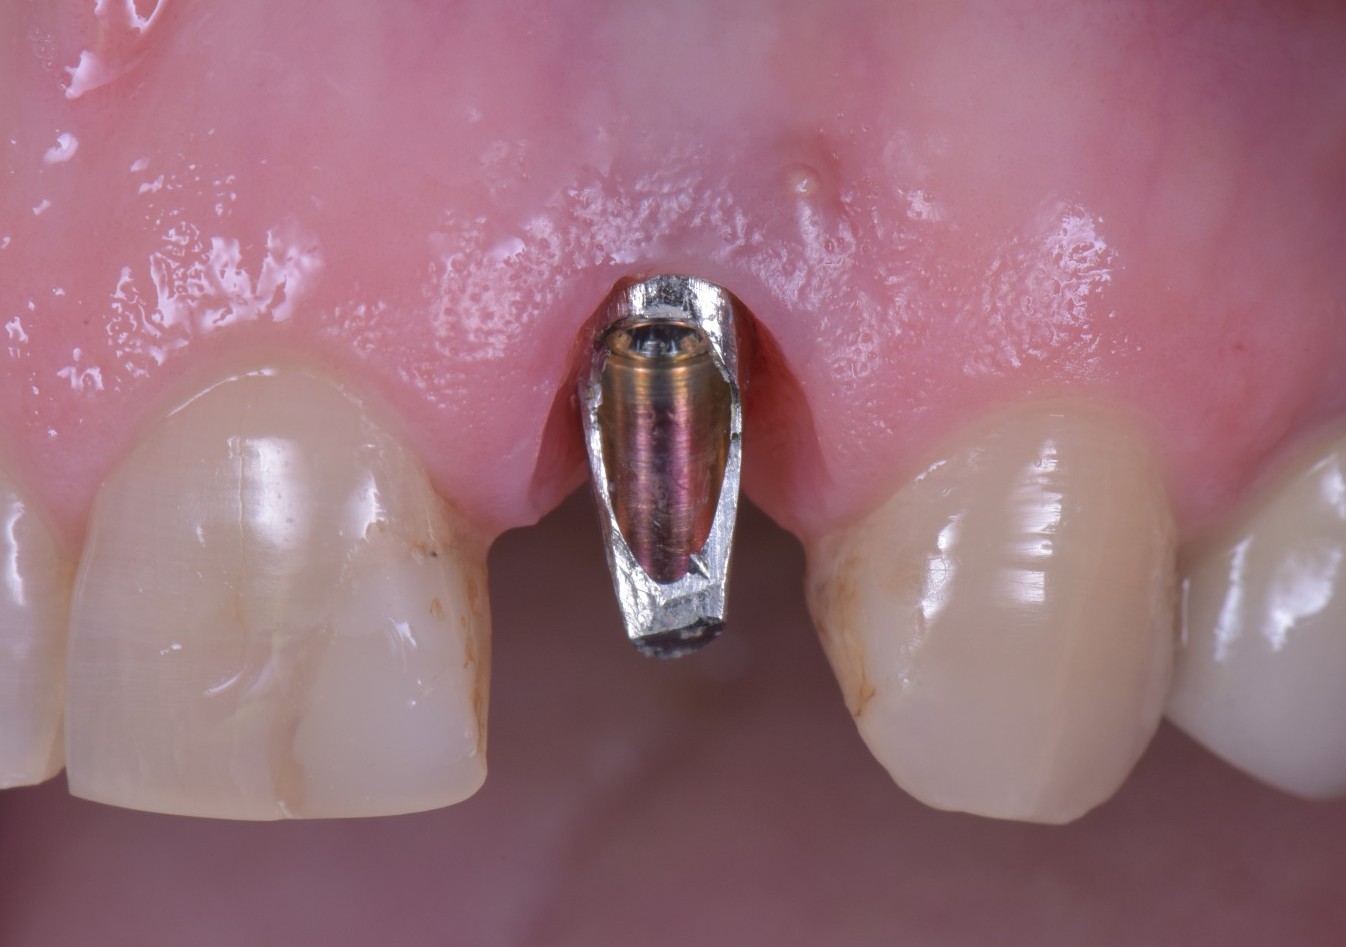

Ma torniamo alla fistola di Rosetta. I tessuti molli non devono essere rispettati e gestiti solo in fase chirurgica ma anche in fase protesica. Se il tuo rispetto della biologia è quello che vedi qua sotto, una fistola sarà la cosa meno grave che ti potrà capitare.

Osserva:

- La rifinitura del moncone.

- La pulizia del moncone nella zona a stretto contatto con l’osso.

- La precisione del provvisorio.

- L’invasione dei tessuti da parte del margine di preparazione con impossibilità assoluta di gestire l’interfaccia di cementazione.